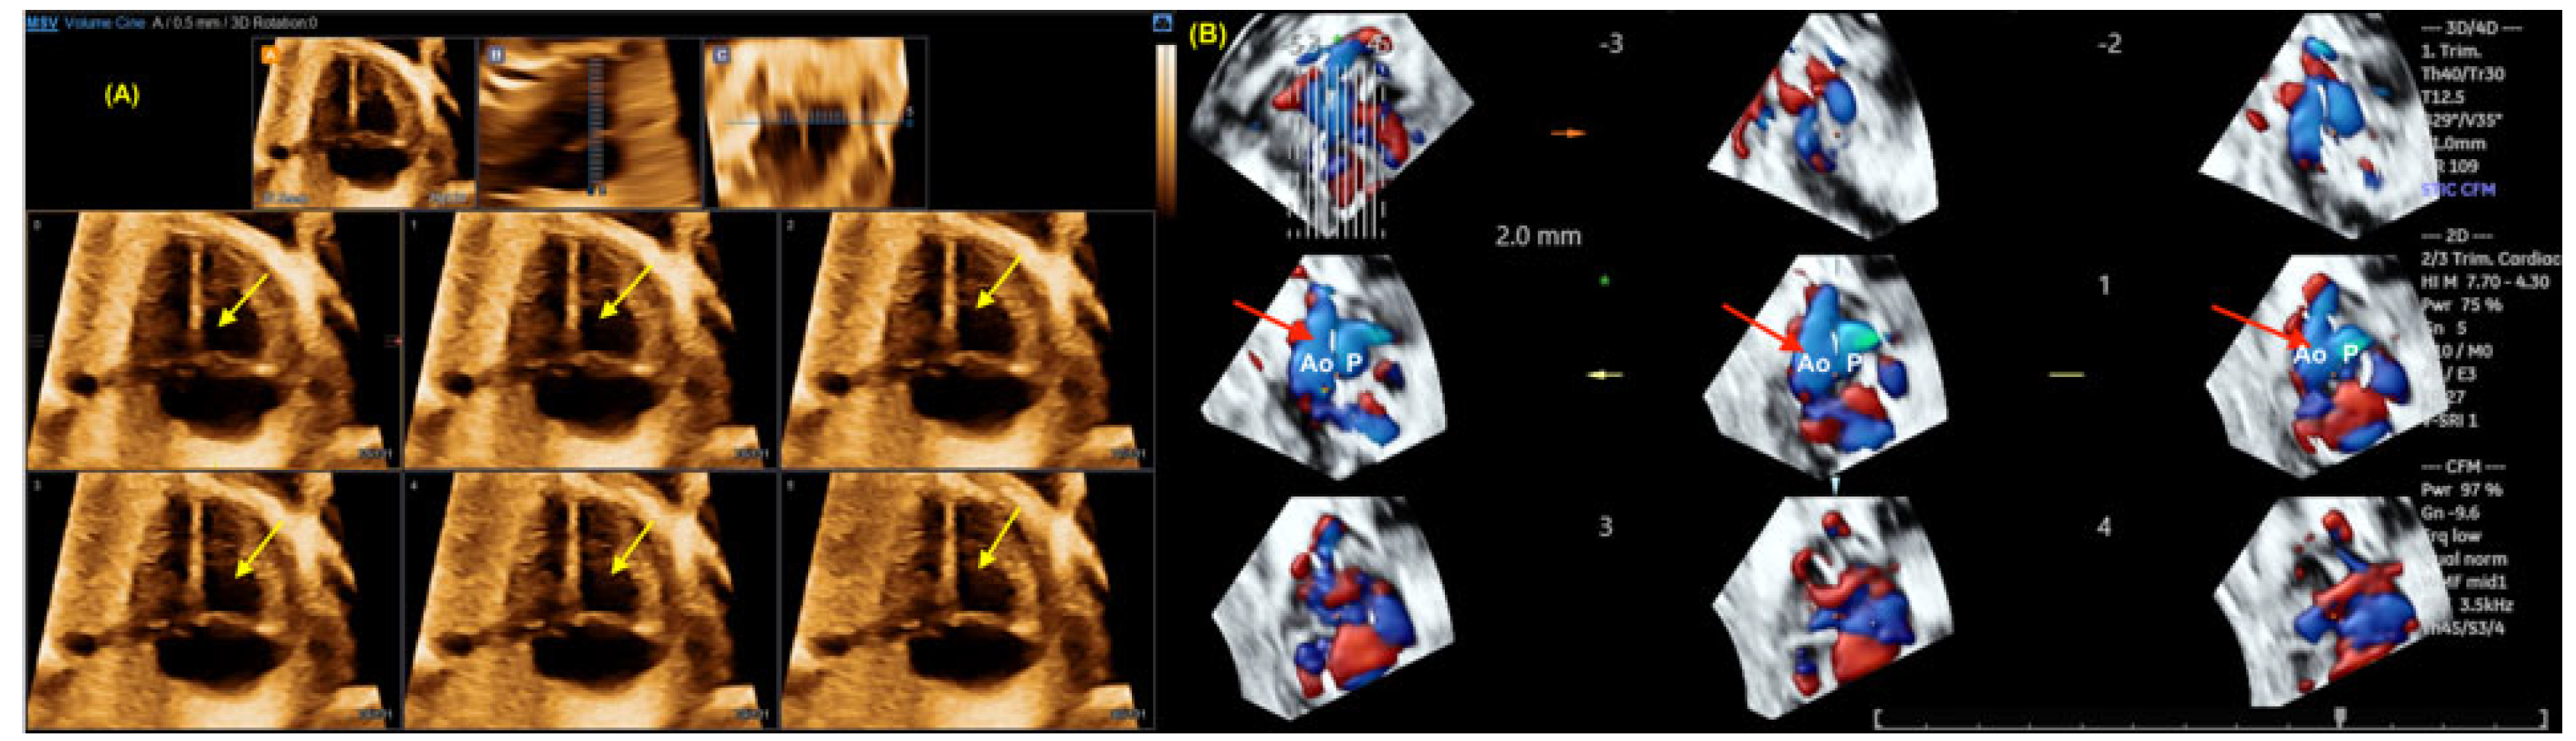

- Rizzo G, Capponi A, Vendola M, Pietrolucci ME, Arduini D. Role of tomographic ultrasound imaging with spatiotemporal image correlation for identifying fetal ventricular septal defects. J. Ultrasound Med. 2008, 27, 1071–1075.

- Liu J, Wang Y, Zhao H, Liu W. Spatio-temporal image correlation rendering mode visualizes the specific location and surrounding structure of ventricular septal defect. Clin Anat. 2019, 32, 408–420.

- Pontes ALS, Chagas CC, Bravo-Valenzuela NJ, Peixoto AB, Mappa I, Rizzo G; et al. Fetal heart foramen ovale area by three-dimensional ultrasound using stic in the rendering mode: Reference range and applicability in congenital heart diseases. Int J Cardiovasc Imaging. 2023, 39, 531–539.